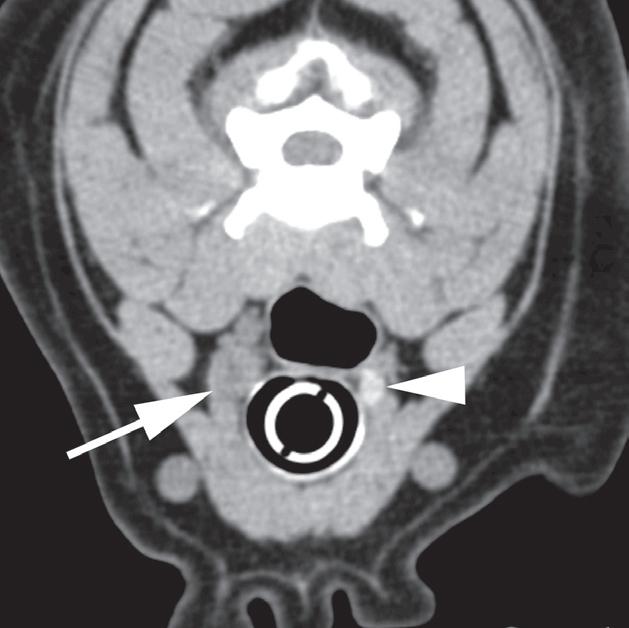

Badanie wykonano u 7-letniego rottweilera z rozpoznanym guzem nadnercza oraz nagłymi objawami dyskomfortu jamy brzusznej. Obrazy na ryc. a–c uporządkowano od strony doczaszkowej do doogonowej. Nadnercze prawe jest powiększone (a, d – otwarty grot strzałki) i ma widoczną ekscentryczną komponentę torbielowatą o densyjności płynu, która rozchodzi się doogonowo (a, b – strzałki). Tkanka miękka rozrostu oraz torebka nadnercza wykazują obwodowe wzmocnienie pokontrastowe. Torbielowata komponenta zmiany rozrostowej widoczna na obrazie odpowiada krwotokowi, który rozciąga się doogonowo w przestrzeni zaotrzewnowej (d). Dobrzusznie od zmiany widoczny jest moczowód (b – grot strzałki). Diagnoza makroskopowa i histologiczna została potwierdzona po chirurgicznym usunięciu zmiany (e – strzałka). Proszę zwrócić uwagę na porównanie obrazu TK zmiany (d) z wyciętym preparatem makroskopowym (f)

Rycina 5.6.6. Przysadkowozależna nadczynność kory nadnerczy (pies) TK